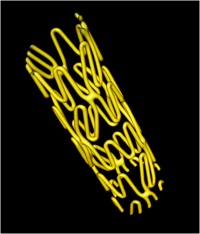

Super Nova系统扫描血管支架CT图像